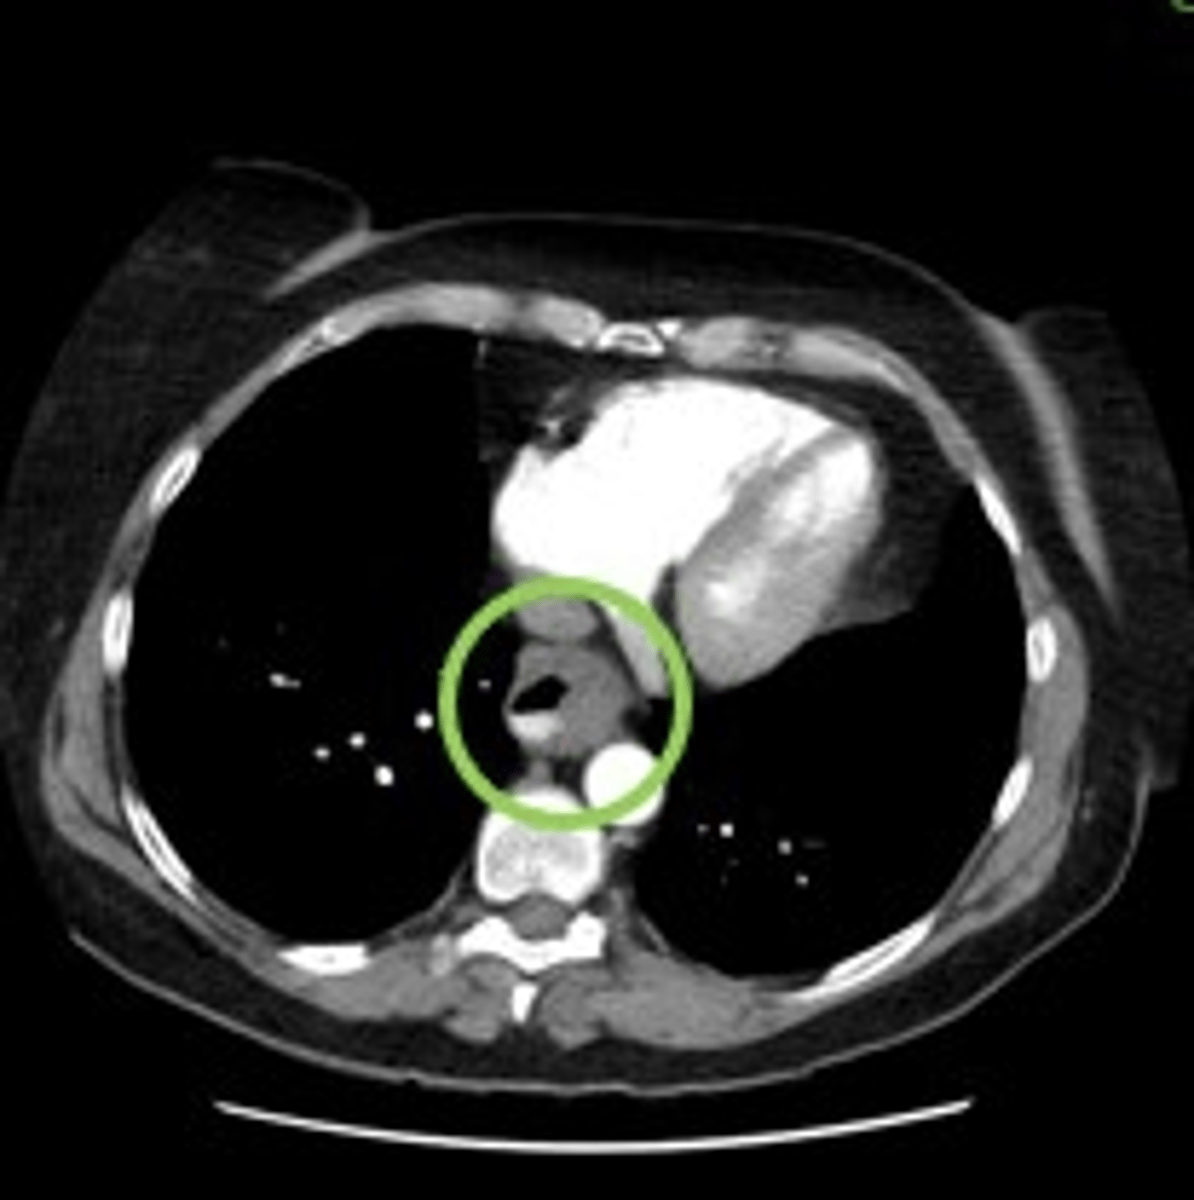

What is a pulmonary embolus (PE)?

A blood clot in the main pulmonary arteries.

What is the most common cause of a pulmonary embolus (PE)?

Blood clots that travel from deep veins in the legs.

How can a pulmonary embolus (PE) be identified on an image?

By looking for dark gray areas within a contrast-filled artery.

Where can a pulmonary embolus (PE) extend to?

Lobar and segmental pulmonary arteries.